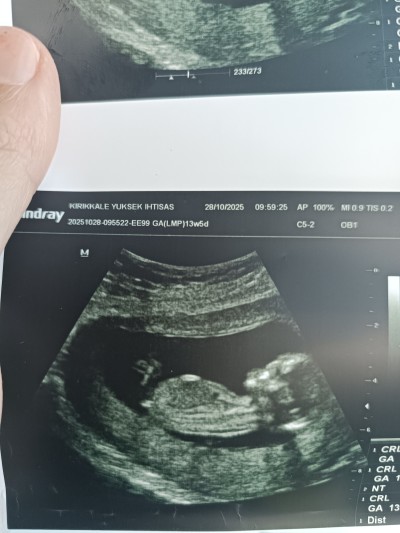

cinsiyet tahmini olan varmi

Gebelik haftası 13+4